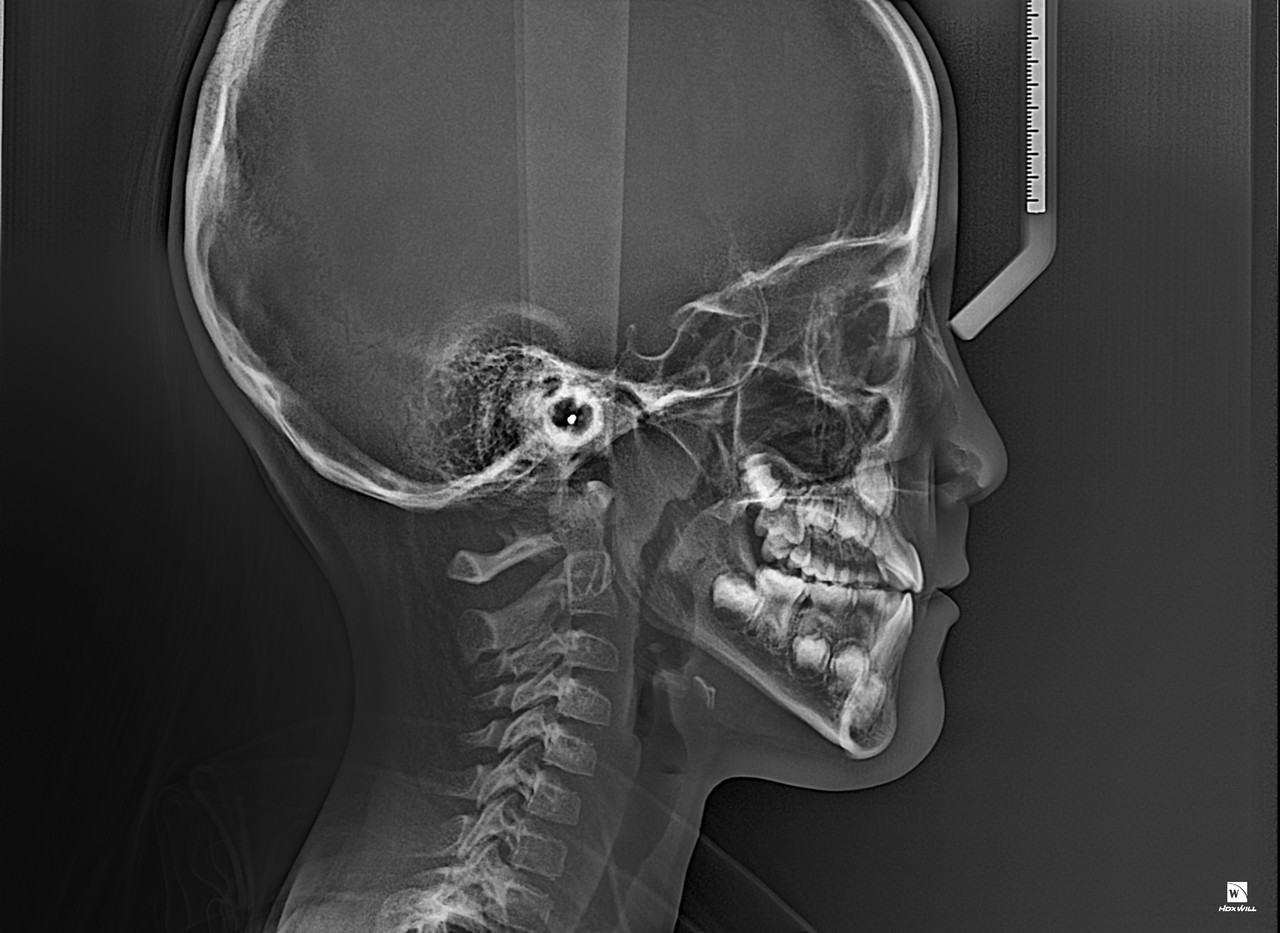

1차 교정(Phase I Orthodontic Treatment)은 혼합 치열기(유치와 영구치가 같이 있는 시기)

또는 초등학교 저학년~중학교 초반 정도의 어린 나이에 진행되는 초기 교정 치료입니다.

목표는 턱의 성장 조절, 심각한 부정교합 예방, 공간 확보, 습관 개선 등 입니다.

턱 성장 유도 및 조절

아래턱 또는 위턱이 지나치게 앞으로 나오거나 뒤로 들어간 경우, 성장기에 맞춰 유도

영구치가 날 공간 확보

유치가 너무 일찍 빠지거나, 공간이 부족해 영구치가 삐뚤게 날 것을 방지

심한 부정교합 예방

심한 반대교합(아래턱이 앞으로 나온 경우)이나 개방교합 등은 조기에 개입 필요

구강 습관 개선

손가락 빨기, 혀 내밀기, 구호흡 등 나쁜 습관으로 인한 부정교합 예방

대부분의 경우 1차 교정 후에도 영구치가 모두 나고 나서 2차 교정(본격적인 전체 교정)이 필요합니다.

1차 교정은 문제를 미리 완화하고, 이후 교정을 더 효율적이고 짧게 만들기 위한 예방적 치료로 볼 수 있습니다.